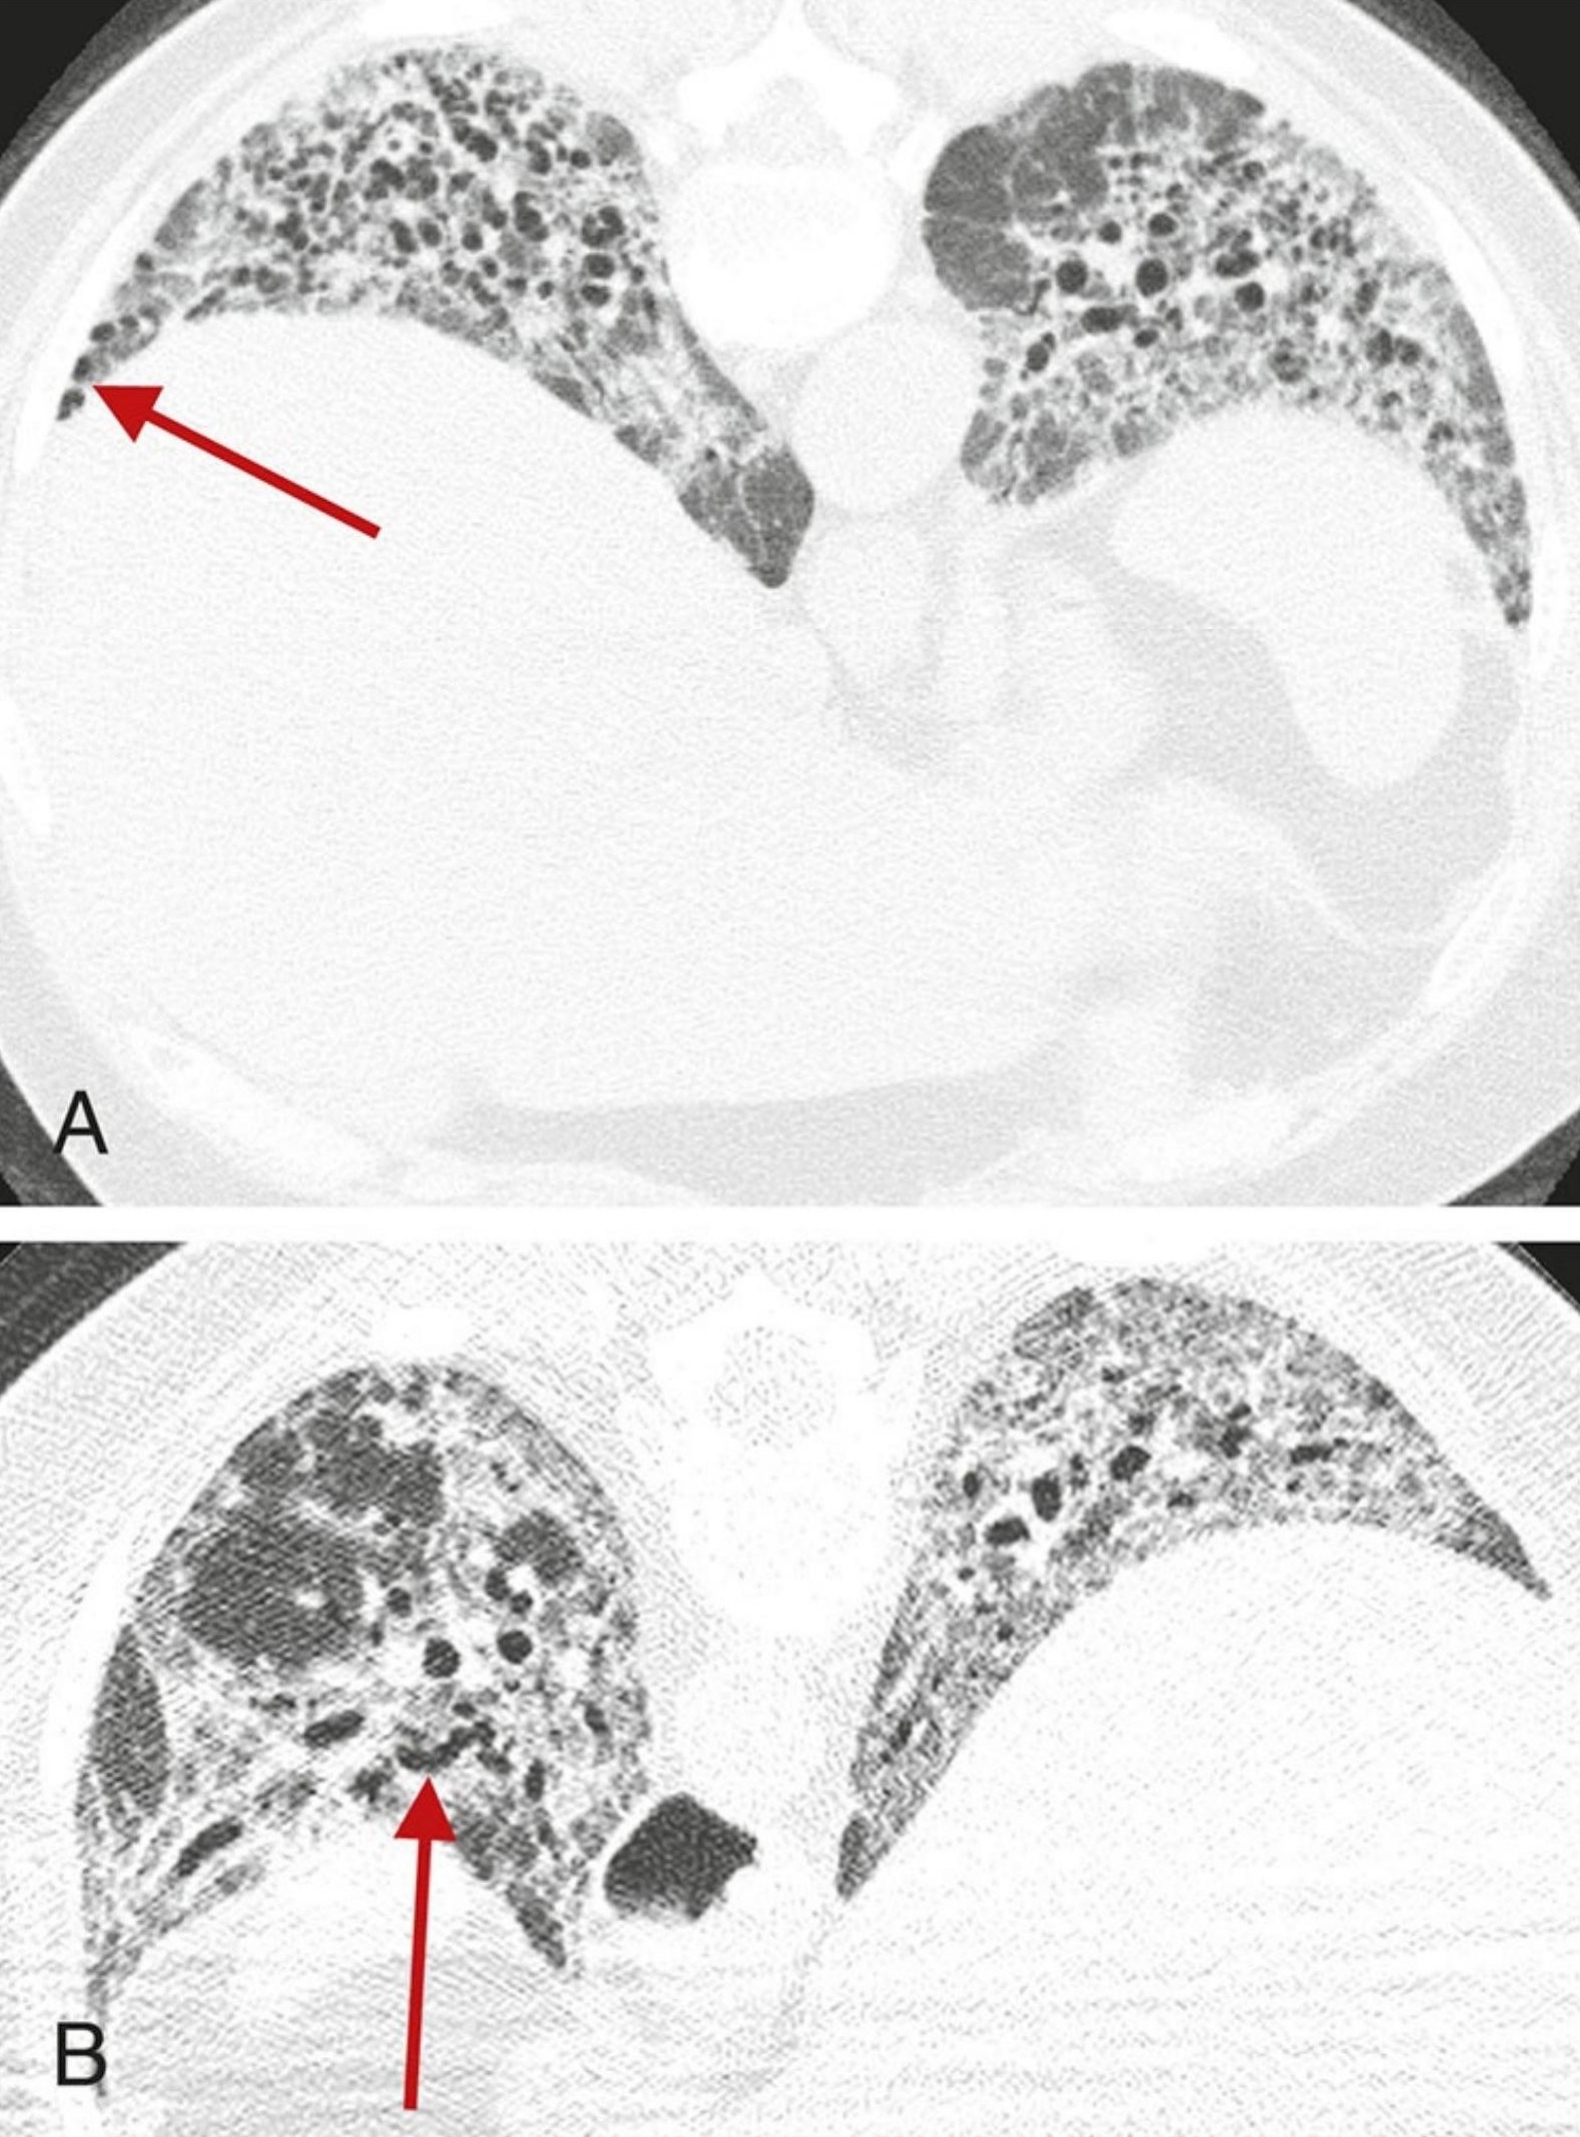

4e03c8cebf92f7f1d801e5412908e0ba.png

细胞型NSIP的典型表现。

4例细胞型NSIP,每例均显示GGO是最明显的异常(箭)。纤维化征象(如牵拉性支气管扩张)无或程度轻微。紧邻胸膜下肺区相对不受累(A至C)高度提示NSIP,但是也有许多NSIP病例无此征象(D)。